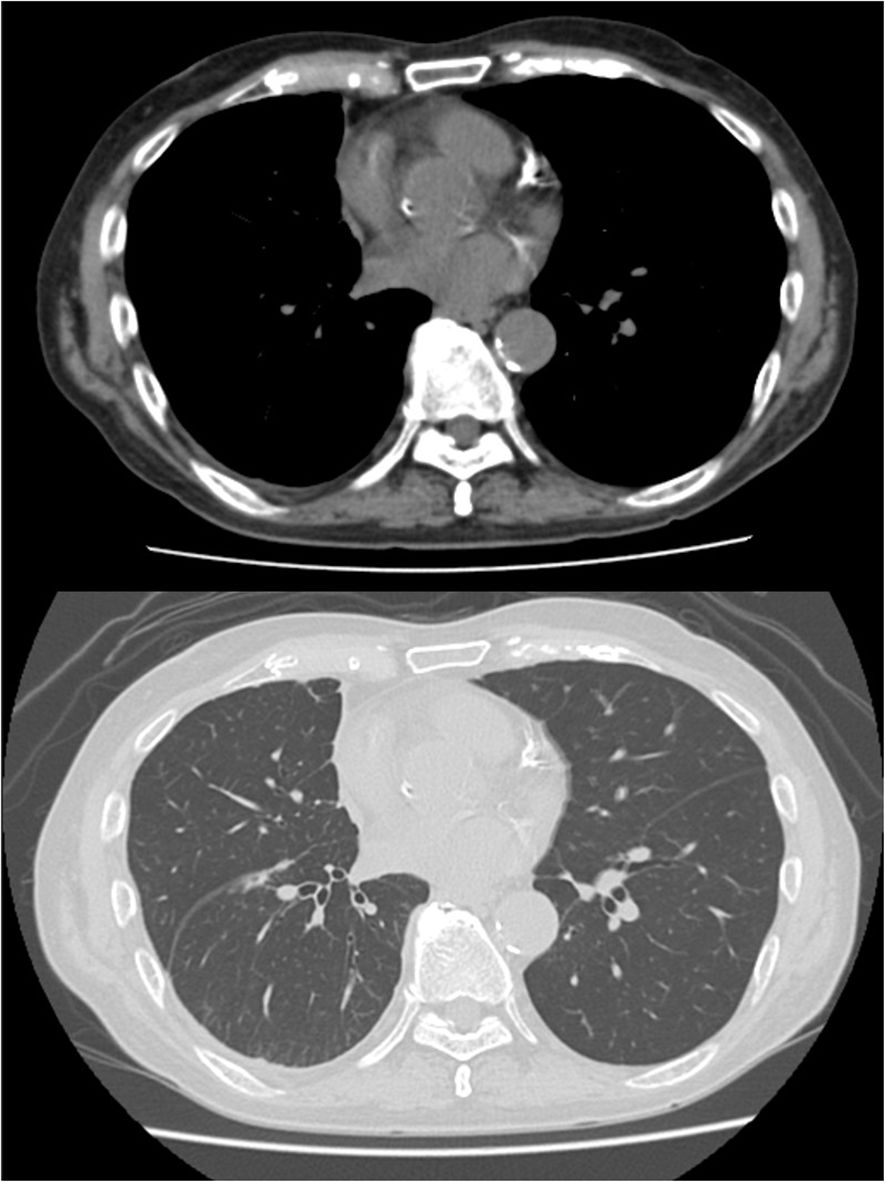

Contrast-enhanced CT imaging for close examination revealed diffuse, slight pleural thickening with contrast enhancement. PET-CT revealed heterogeneous FDG uptake (SUV max 4.0) in the pleura, right paratracheal lymph node, and chest wall, including the interlobar pleura, which showed irregular thickening (Figure 1). Magnetic resonance imaging (MRI) of the brain indicated no metastatic lesion.

Figure 1. Radiological findings of malignant pleural mesothelioma. Positron emission tomography (PET) revealed asymmetric thickening of the right pleura, including the interlobar pleura, with heterogeneous fluorodeoxyglucose (FDG) uptake (peak SUVmax 4.0). Abnormal FDG accumulation was also observed in an enlarged lymph node-like structure located anterior to the right brachiocephalic vein and contiguous with the thickened pleura. Additionally.